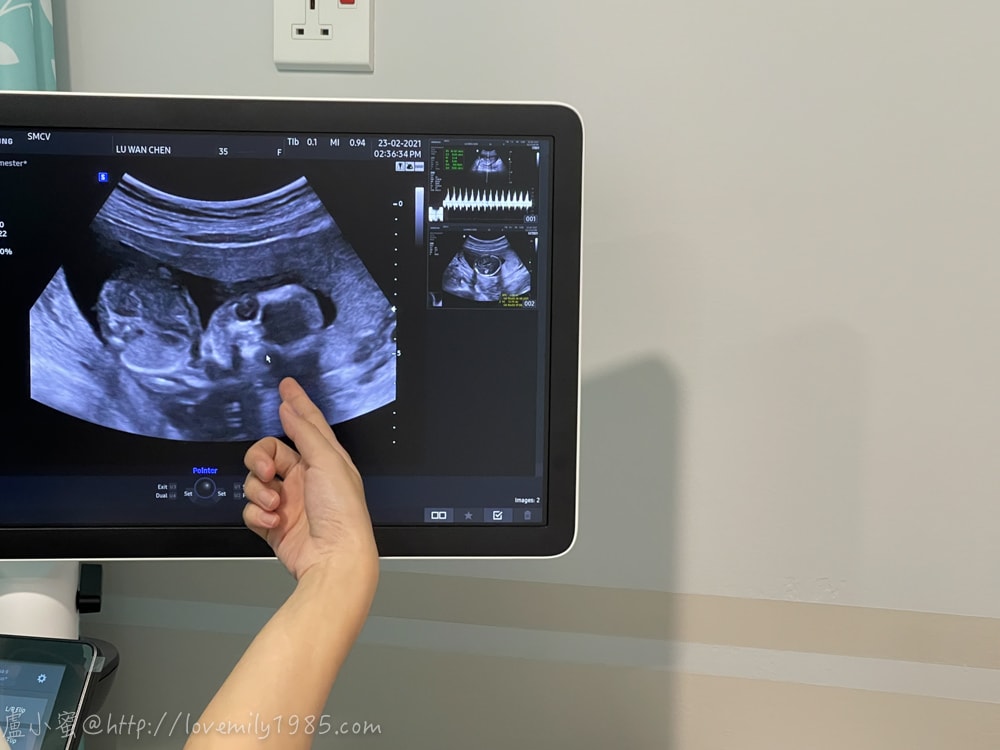

這週數的超音波~真的還是好像抽象畫啊!

我請胖子拍,他一度不知道要拍什麼,他說因為他看不出來,噗

是說我也是用盡想像力,這邊是眼睛,是不是很難懂

目前三寶138g

根據BPD雙頂徑、HC頭圍、AC腹圍、FL大腿骨長綜合結果,推測週數16W1D

跟目前週數15W5D差不多,正常穩定的長大中(拍手)